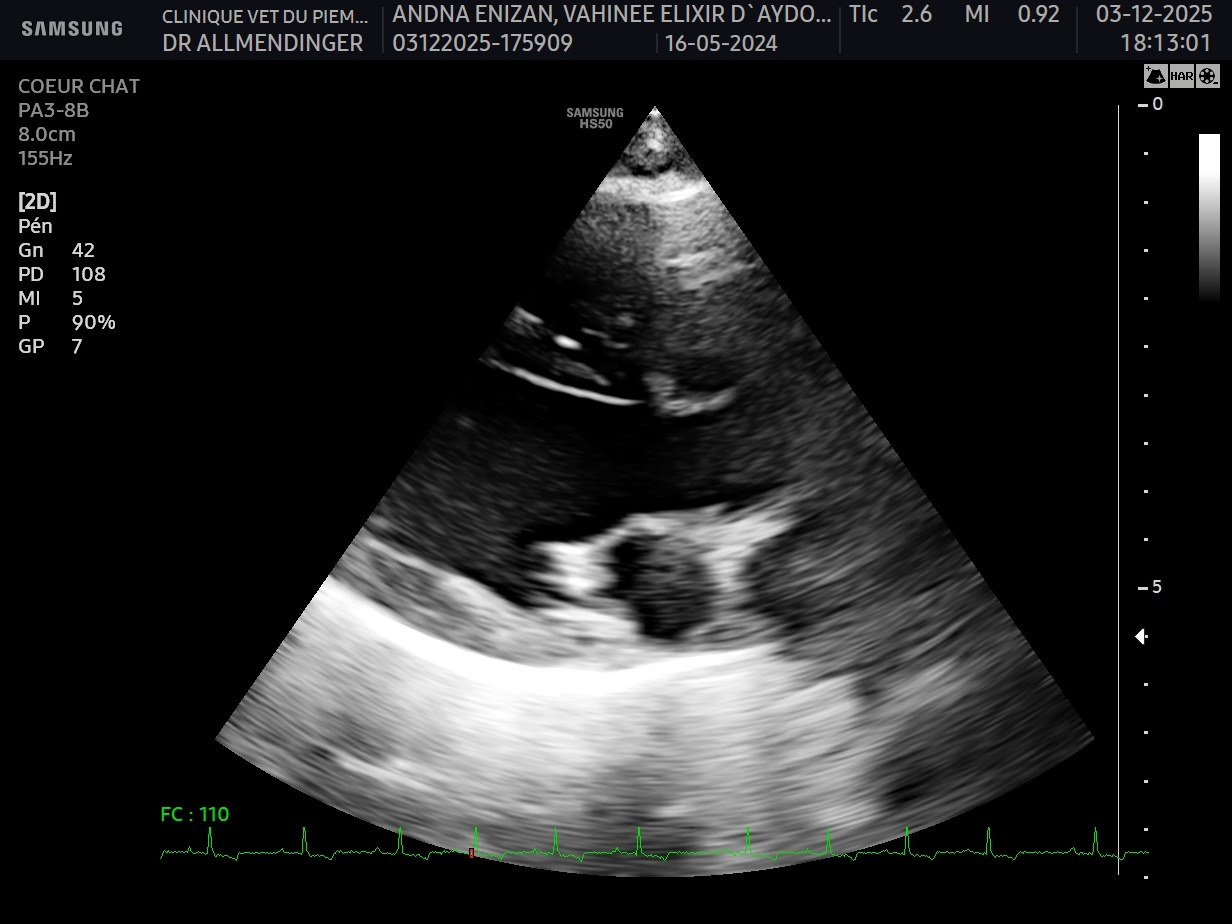

Geste technique : Mesure échographique du LA/Ao (rapport oreillette gauche/aorte)

- Connaître les principales causes de souffle chez le chat et leuyr prévalence

- Connaître les limites de l’examen sanguin pour l’exploration d’un souffle asymptomatique chez le chat

- Connaître les risques associée à la présence d’une CMH asymptomatique chez le chat